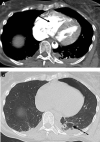

Tetralogy of Fallot (TOF) is a heterogeneous congenital heart disease that is occasionally diagnosed during adulthood. However, although they are often asymptomatic, adult patients with uncorrected TOF often have a poor prognosis. Poor outcomes indicate the importance of the identification and management of these patients, especially in the context of intercurrent disease or noncardiac surgery. We describe a case of clinically silent TOF in a 51-year-old woman. TOF was unmasked during a major noncardiac surgery for a polytrauma and successfully treated with the cooperation of a multidisciplinary team. (Level of Difficulty: Advanced.).